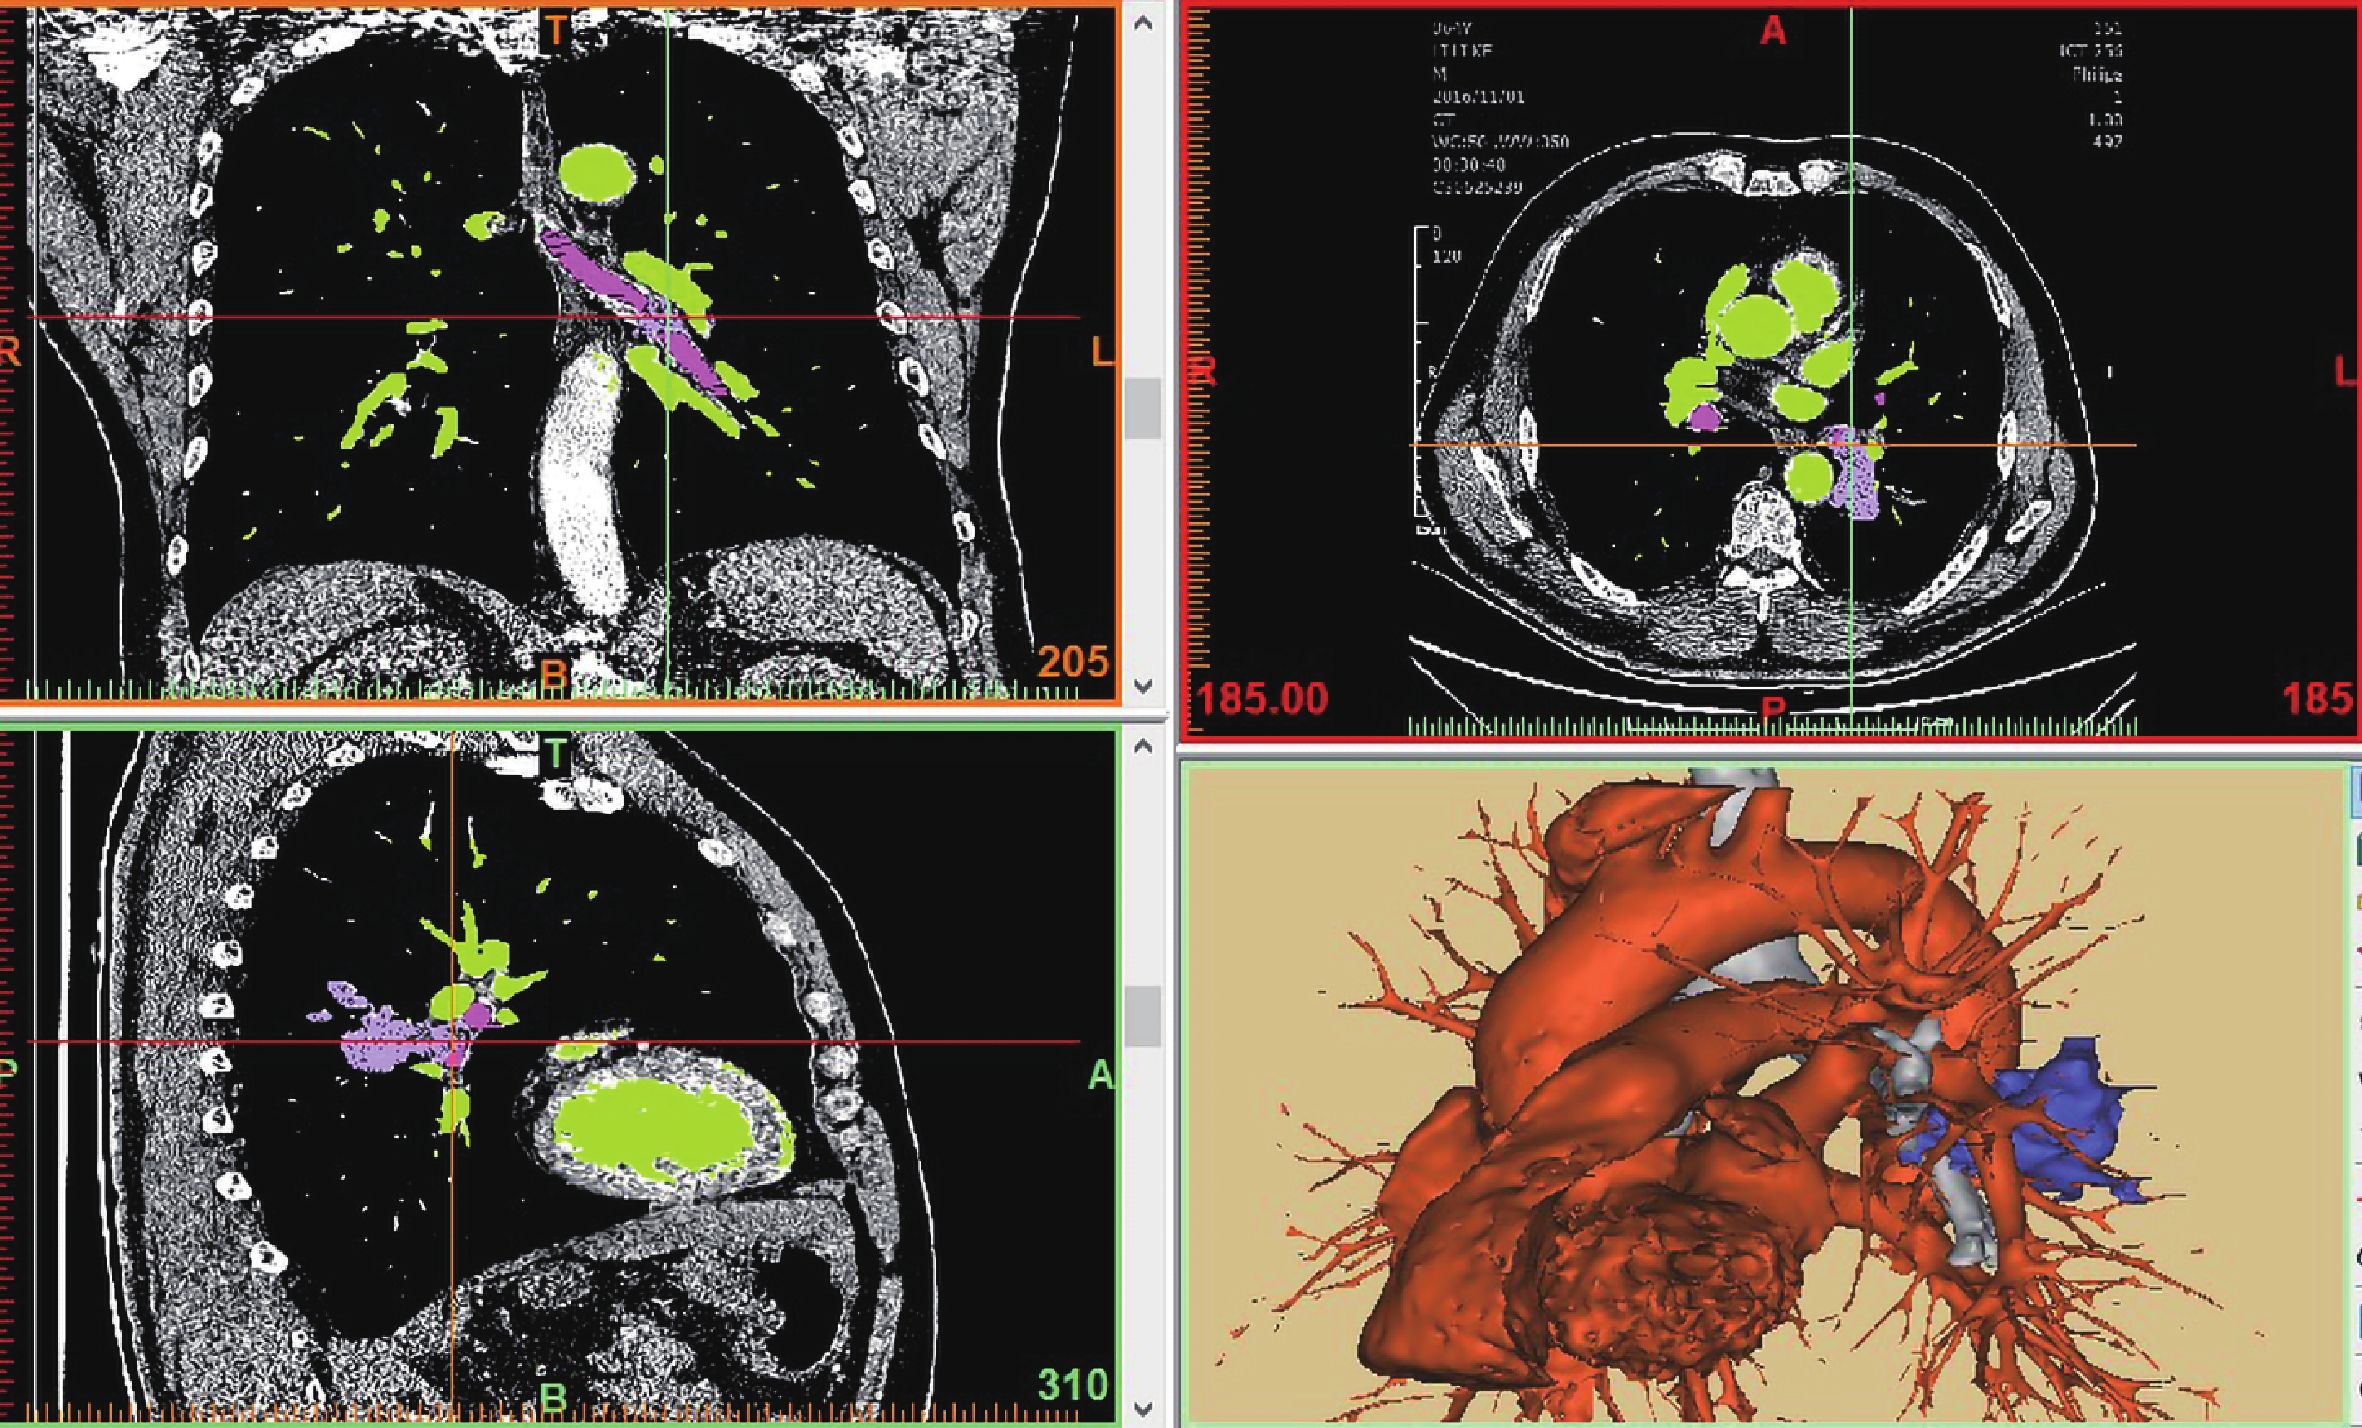

術前兩組均給予患者胸部血管增強 CT,區分血管及組織,層厚 1 mm,將試驗組 CT 圖片以 DICOM 格式導入 Mimics-17.0 程序進行 3D 重建(圖 1),術前根據患者 3D 重建圖像模擬手術科內會診,評估腫物侵犯范圍,測量安全距離,行模擬手術(圖 2),選取準備切除范圍,規避重要血管、氣管等其他組織。

a:3D 重建冠狀位;b:3D 重建矢狀位;c:3D 重建氣管及腫物;d:模擬手術離斷氣管;e:左主支氣管及左上肺支氣管;f:主支氣管-右肺上葉氣管模擬吻合